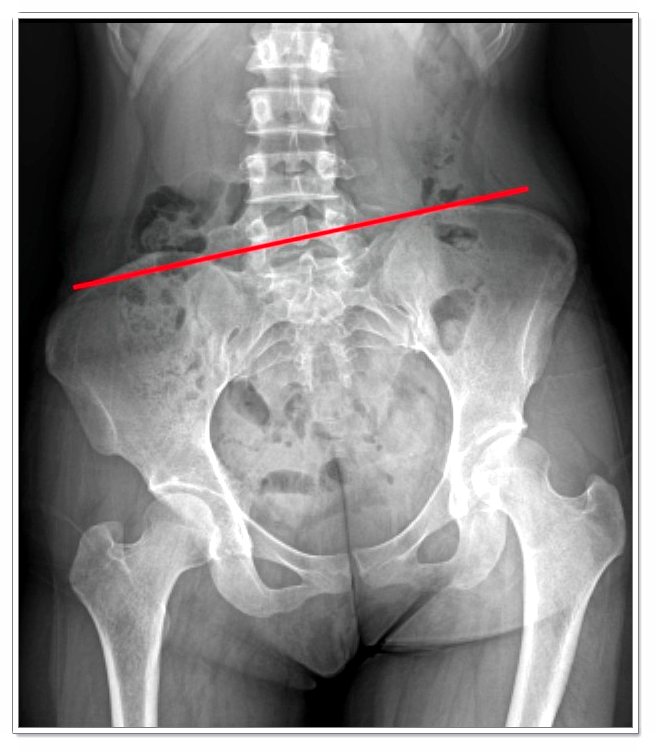

많은 분들이 허리나 골반 통증이 있을 때 ‘뭔가 문제가 있나?’ 하고 의심하곤 하지만,

자세히 보면 골반의 회전이나 틀어짐이 원인인 경우가 많습니다.

골반이 돌아가면 다리 길이에 차이가 생기고, 체중 중심이 한쪽으로 쏠리게 되죠.

이 상태가 오래 지속되면 척추까지 틀어지며 상체 자세에도 영향을 미치게 됩니다.

- 가방을 한쪽 어깨로만 메기

- 다리를 자주 꼬기

- 딱딱한 바닥에 오래 앉기

이런 습관들이 골반 불균형을 악화시키는 주된 원인이 됩니다.

처음엔 불편함이 없어도, 몸이 비대칭으로 굳어가면 연산동체형교정 등의 교정 과정이 점점 까다로워질 수 있습니다.